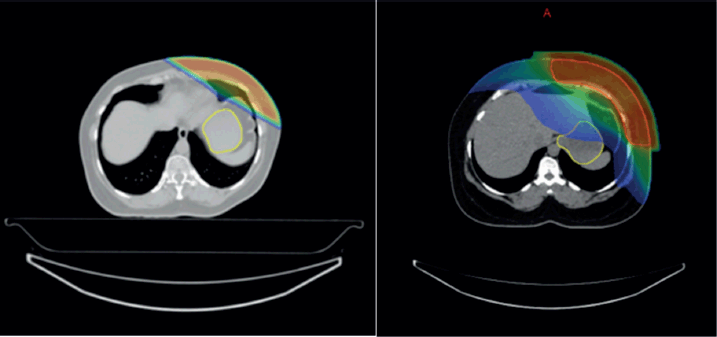

In contrast, no statistically significant difference was found in upper GI toxicity between 3DCRT and IMRT (p = 0.882) or between VMAT and IMRT (p = 0.083), indicating that IMRT does not significantly alter the toxicity profile compared to either 3DCRT or VMAT (Table 4) (Supplementary Figure 3a and b).

Supplementary Figure 3. (a and b): Isodose curves showing dose distribution between two RT techniques 3DCRT and IMRT.